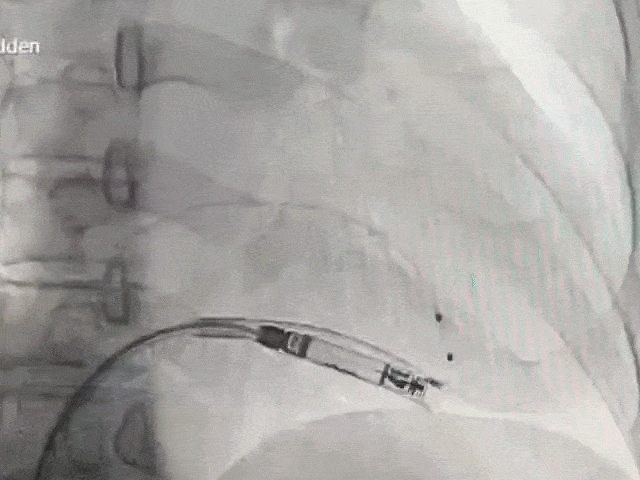

手术过程部分展示

猪尾造影,明确右室心尖、前室间沟、后室间沟、三尖瓣相对位置

右前30°造影,位置理想

左前45°造影贴靠间隔